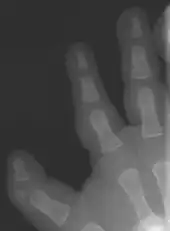

Triphalangeal thumb (TPT) is a congenital malformation where the thumb has three phalanges instead of two. The extra phalangeal bone can vary in size from that of a small pebble to a size comparable to the phalanges in non-thumb digits. The true incidence of the condition is unknown, but is estimated at 1:25,000 live births.[1] In about two-thirds of the patients with triphalangeal thumbs, there is a hereditary component.[2] Besides the three phalanges, there can also be other malformations. It was first described by Columbi in 1559.[3]

The triphalangeal thumb has a different appearance than normal thumbs. The appearance can differ widely; the thumb can be a longer thumb, it can be deviated in the radio-ulnar plane (clinodactyly), or thumb strength can be diminished. In the case of a five-fingered hand it has a finger-like appearance, with the position in the plane of the four fingers, thenar muscle deficiency, and additional length. There is often a combination with radial polydactyly.

There are multiple classifications for the triphalangeal thumb. The reason for these different classifications is the heterogeneity in appearance of the TPT. The classification according to Wood [9] describes the shape of the extra phalanx: delta (Fig. 4), rectangular or full phalanx (Table 1). With the classification made by Buck-Gramcko a surgical treatment can be chosen (Table 1). Buck-Gramcko differentiates between six different shapes of the extra phalanx and associated malformations.[10]